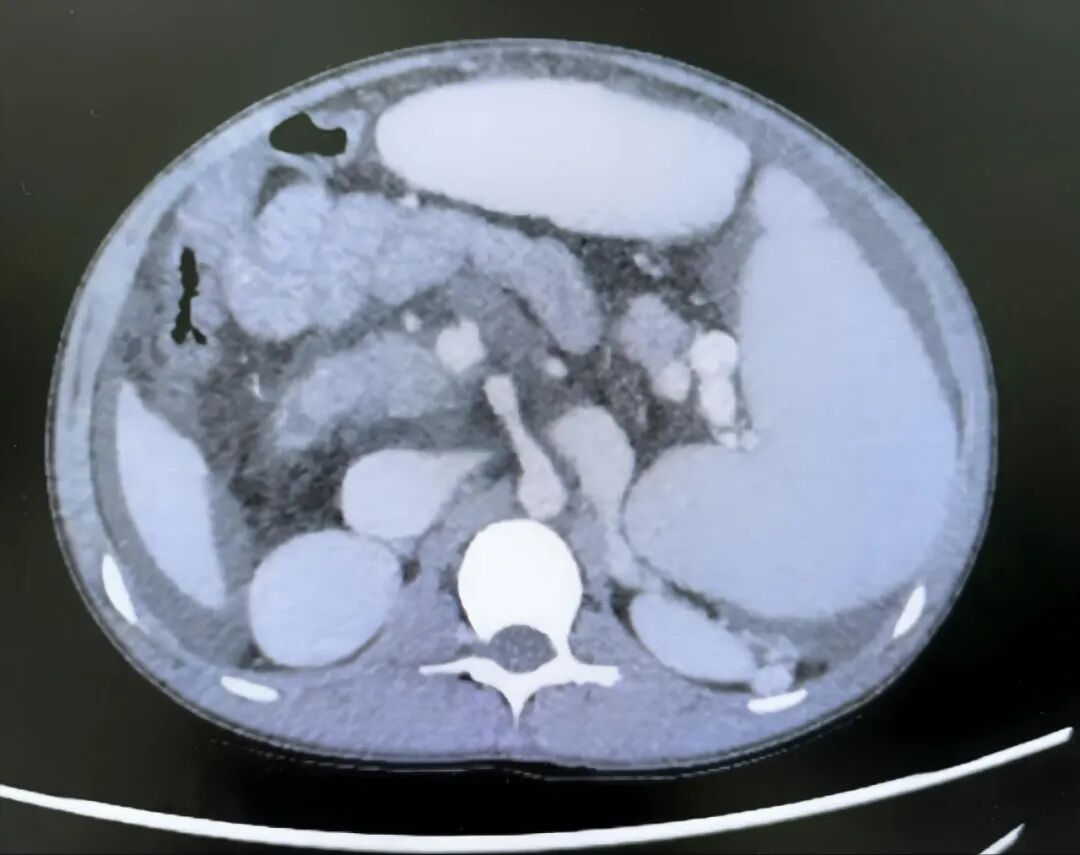

入院后血液检查结果显示,小李患有极重度贫血,血红蛋白仅25g/L(正常参考值120g/L以上),已处于休克边缘;血小板计数极度低下,仅16×10⁹/L(正常参考值100-300×10⁹/L)。影像学检查提示,其脾脏异常巨大,边缘已从腹腔左侧延伸至右侧,占据腹腔大部分空间。

住院期间,小李完善了超声及增强CT检查,明确诊断为门静脉海绵样变,其脾脏肿大程度在门脉高压患儿中极为罕见,此类巨大脾脏通常多见于血液系统疾病患儿。为排除血液系统疾病,团队联系血液科会诊,结合骨髓穿刺结果及血液病相关血液筛查报告,最终排除血液系统疾病可能,确认脾大、脾亢症状仍由门静脉海绵样变所致门脉高压引起。

图1 CT显示脾脏显著增大